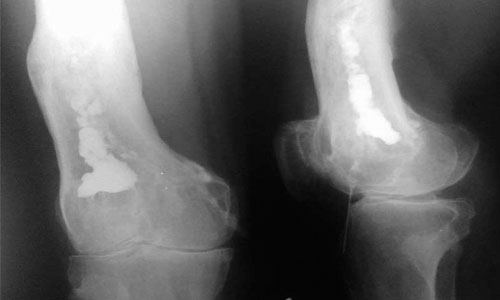

Спустя 2-3 дня появляются локальные симптомы. В области поражения возникают отечность, боль, скованность движений, а кожа становится красной. Чаще всего воспаление затрагивает бедренную и большеберцовую кости нижних конечностей, а также лучевую, локтевую и плечевую кости верхних конечностей. Реже остеомиелит развивается в костных тканях стоп, кистей, таза, ребер, позвоночника, лопаток и ключиц. Для наглядности можно ознакомиться с фотографиями воспаленных участков.

Хроническая форма остеомиелита требует более сложного подхода к лечению. Возможно, потребуется провести ряд обследований и длительную терапию. Лечением таких пациентов занимается хирург. Для подтверждения воспалительного процесса в костях используются различные методы:

- лучевая диагностика: компьютерная томография (КТ), рентген, магнитно-резонансная томография (МРТ);